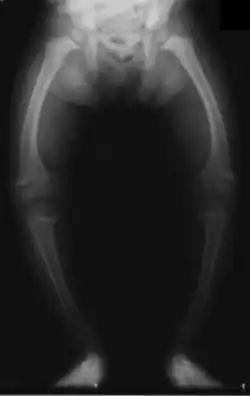

Dítě trpící křivicí na rentgenu

U kojence měknou kosti lebeční, zvláště týlní. Zuby rostou nepravidelně a jsou na kousacích plochách zoubkované, tvrdé patro je vysoko klenuté. Na žebrech je přechod části chrupavčité v kostní značně ztluštělý a tvoří tzv. rachitický růženec. I na ostatních kostech jsou hranice chrupavky a kosti zduřelé, kosti dolních končetin se ohýbají, dítě přestává chodit. Také obratle se hroutí a tím vznikají různé zkřiveniny páteře.